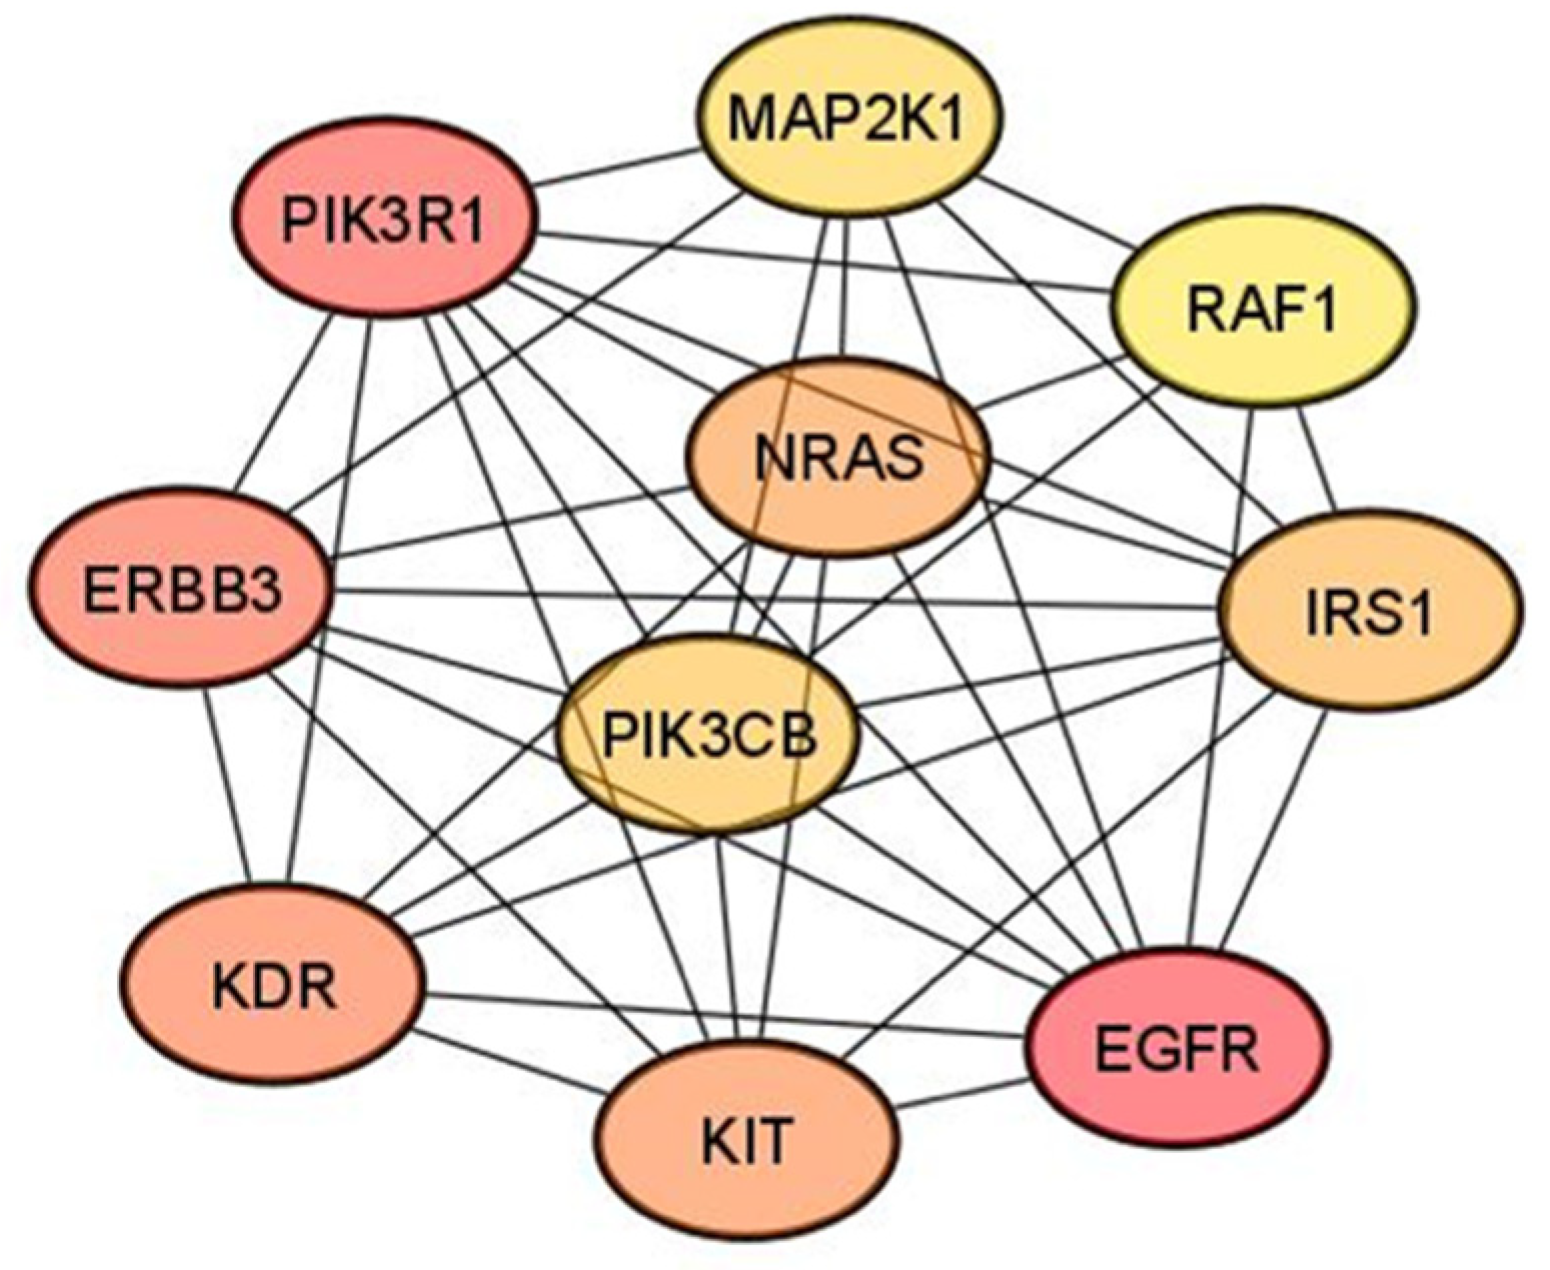

3.4. Hub Gene Identification

| Hub Gene | DEMs Targeting Hub Gene |

|---|---|

| MAP2K1 | miR-152-3p; miR-15a-5p; miR-34a-5p |

| RAF1 | miR-15a-5p; miR-7-5p |

| IRS1 | miR-15a-5p; miR-7-5p |

| EGFR | miR-152-3p; miR-221-3p; miR-222-3p; miR-7-5p |

| KIT | miR-152-3p; miR-221-3p; miR-222-3p |

| PIK3CB | miR-146b-5p; miR-7-5p |

| NRAS | miR-146b-5p; miR-152-3p |

| KDR | miR-15a-5p; miR-221-3p; miR-222-3p |

| ERBB3 | miR-152-3p; miR-221-3p; miR-222-3p |

| PIK3R1 | miR-15a-5p; miR-221-3p; miR-222-3p |